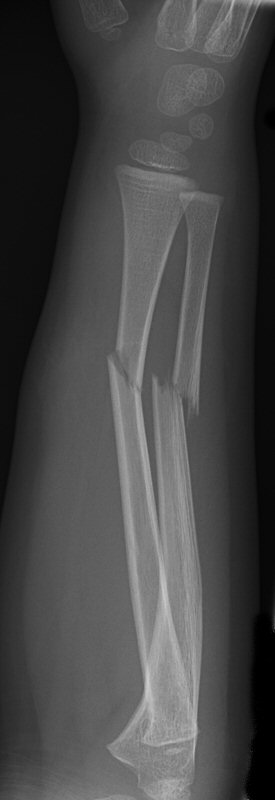

Exempel på rötngenbilder vid TEN-spikning:

Frontalbilder före och efter operation, resp. sidobilder före och efter operation med TEN-spikning i radius och ulna